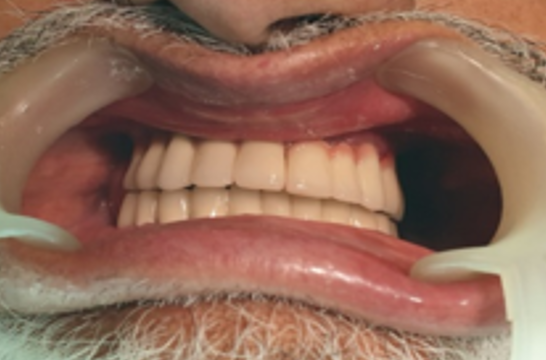

Implant-Retained Overdentures

Oral Health Management for Seniors

Dentures anchored by implants for improved stability in elderly patients

ORAL HEALTH MANAGEMENT FOR SENIORS SEEKING ECONOMICAL SOLUTIONS: A Stable, Cost-Effective Solution

Implant-supported Denture is securely anchored to the jawbone with dental implants, offering enhanced stability compared to traditional dentures that rest on the gums.

Enhanced Stability: Only 2 to 4 implants are typically needed to stabilize a full denture (12-14 teeth), providing a secure fit with significant cost reduction compared to full-mouth fixed _Implants.